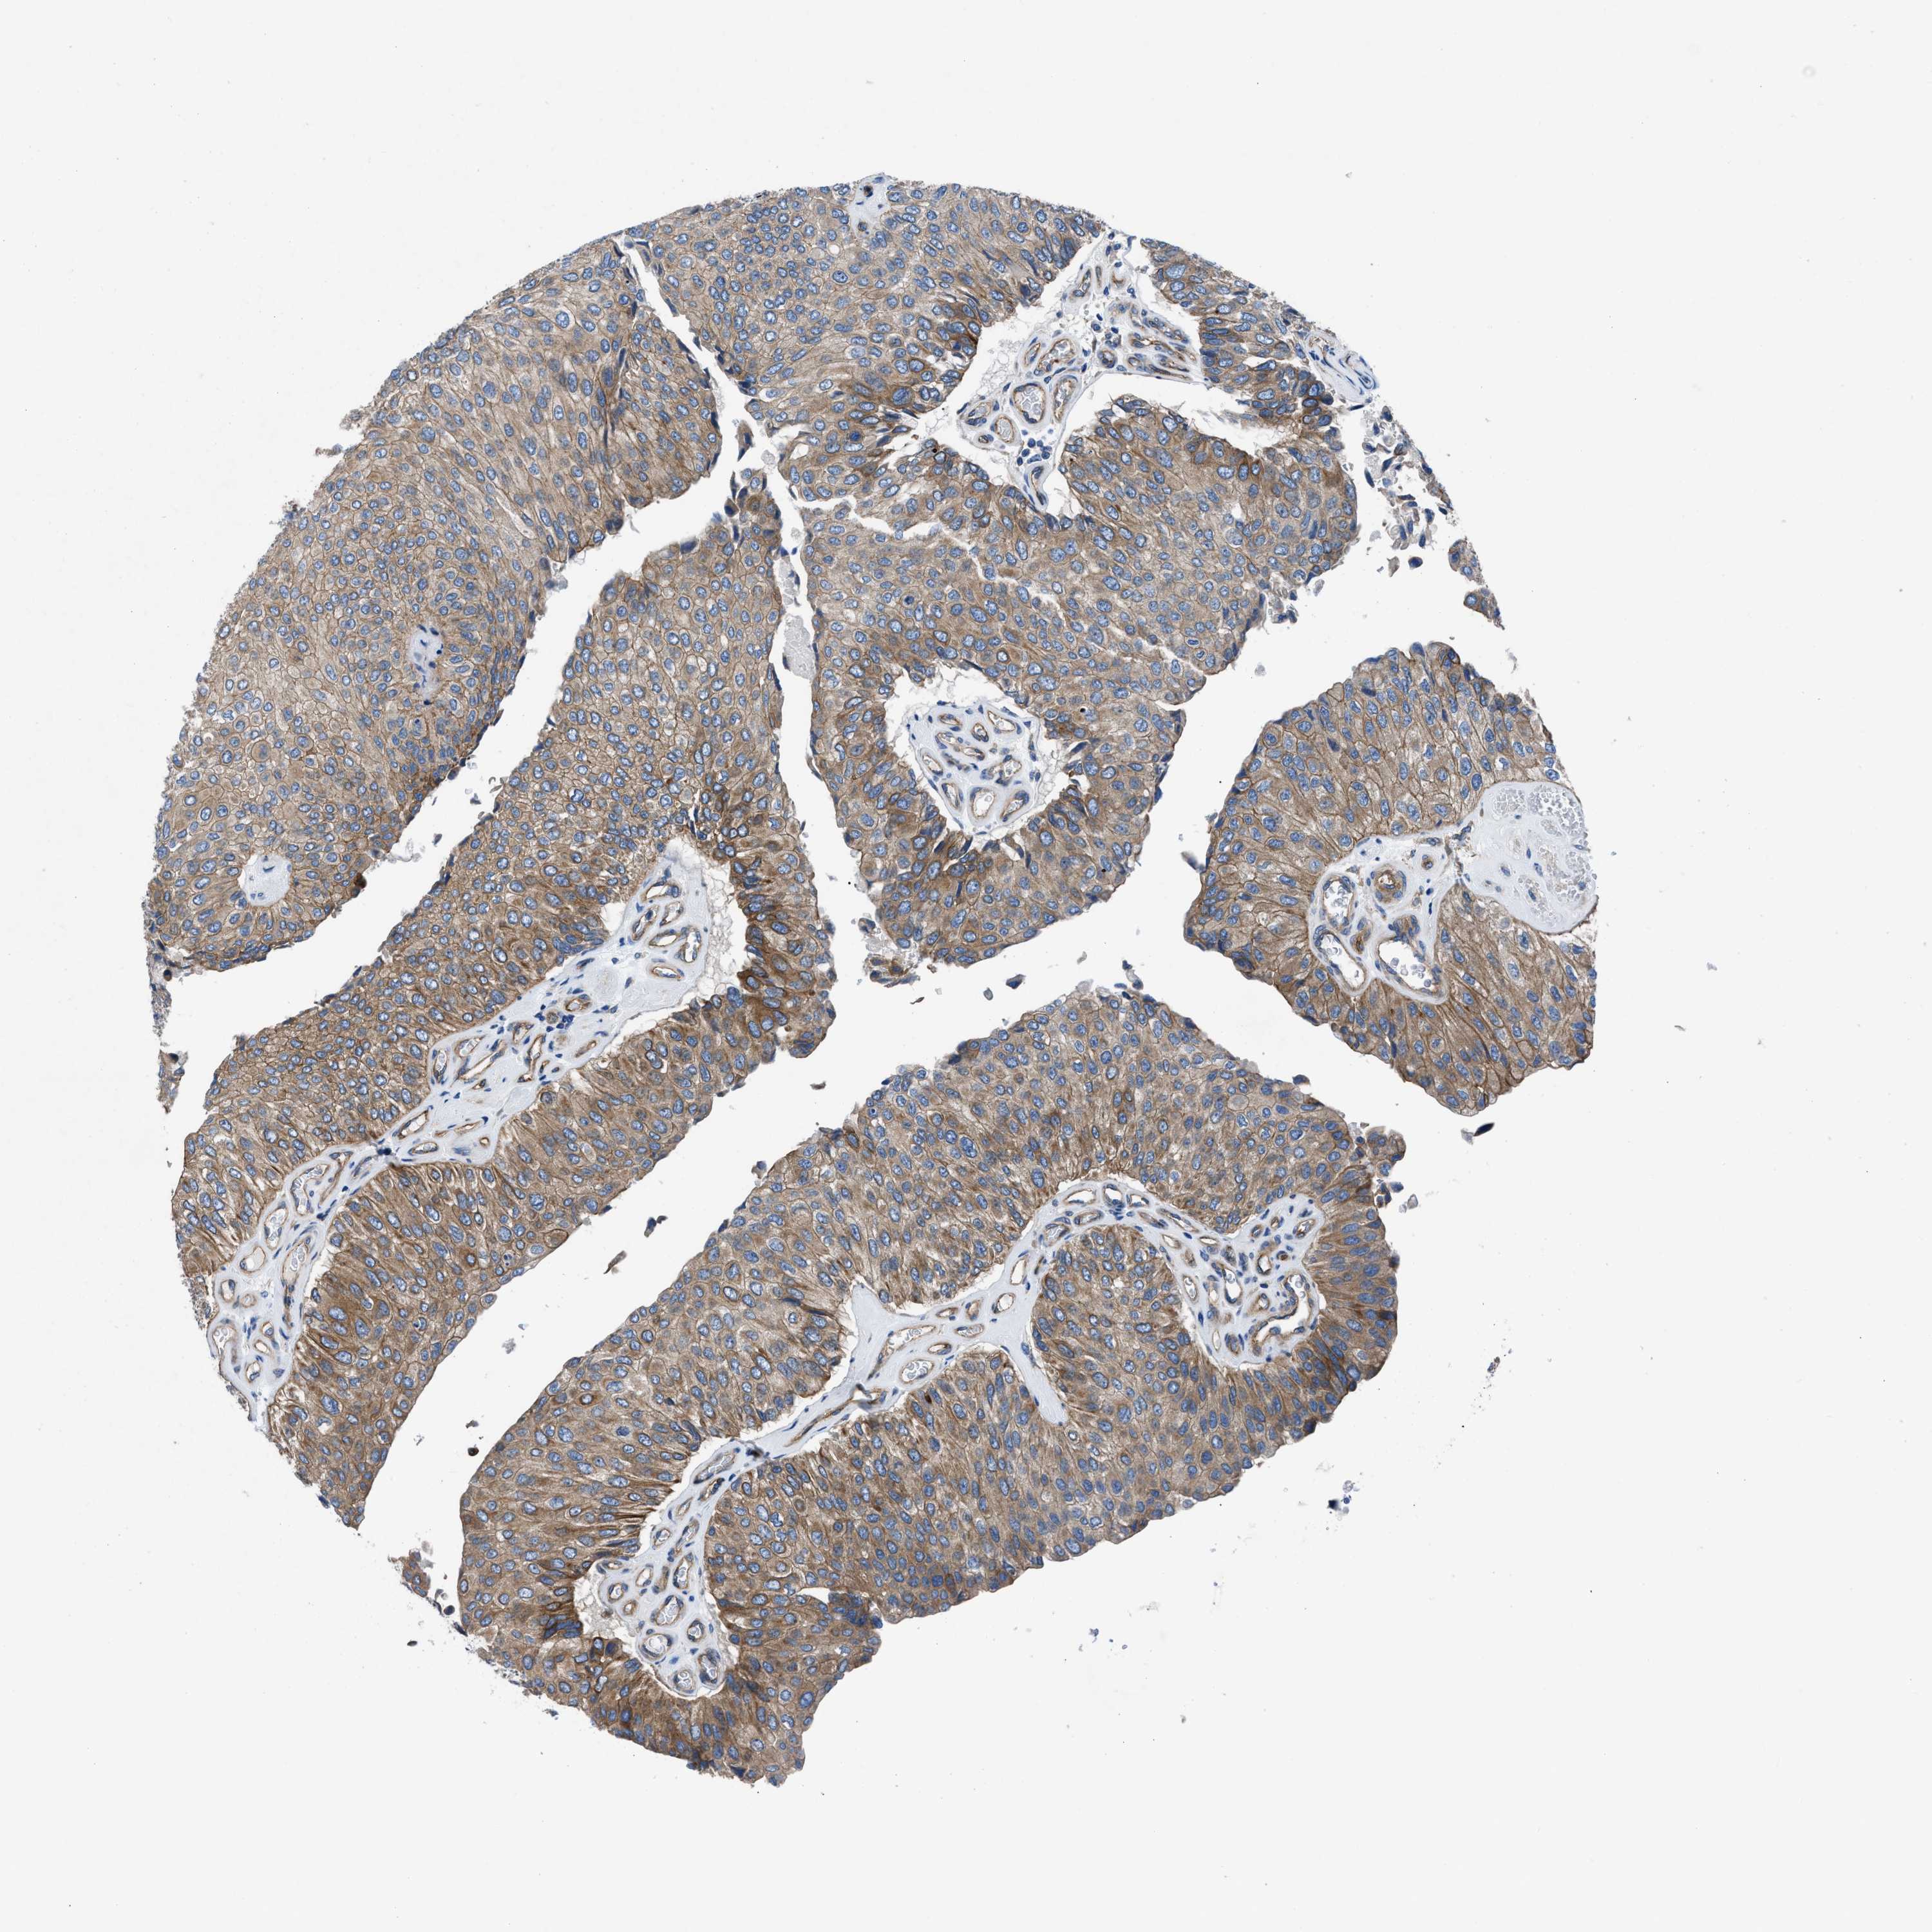

UROTHELIAL CANCER - Protein expressioni

A mouse-over function shows sample information and annotation data. Click on an image to view it in a full screen mode. Samples can be filtered based on level of antibody staining by selecting one or several of the following categories: high, medium, low and not detected. The assay and annotation is described here.

Note that samples used for immunohistochemistry by the Human Protein Atlas do not correspond to samples in the TCGA dataset.

Antibody stainingi

Antibody staining in the annotated cell types in the current human tissue is reported as not detected, low, medium, or high, based on conventional immunohistochemistry profiling in selected tissues. This score is based on the combination of the staining intensity and fraction of stained cells.

Each image is clickable and will lead to virtual microscopy that enables deeper exploration of all samples and also displays staining intensity scores, fraction scores and subcellular localization as well as patient and tissue information for each sample.

Antibody HPA016605

Staining

High

Medium

Low

Not detected

Intensity

Strong

Moderate

Weak

Negative

Quantity

>75%

75%-25%

<25%

None

Location

Nuclear

Cytoplasmic/membranous

Cytoplasmic/membranous,nuclear

Urothelial carcinoma, Low grade

Urothelial carcinoma, High grade